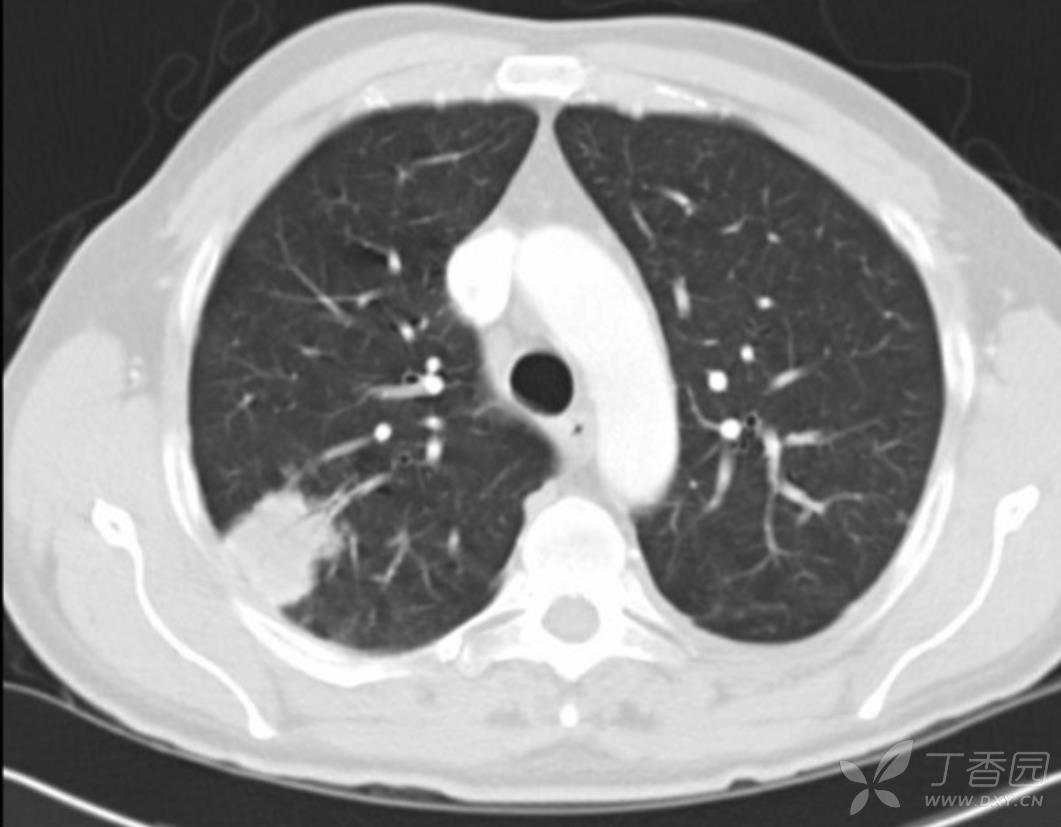

男性,49岁,同性恋。非典型的皮肤损害,无症状的肺结节。右肺上叶3.8cm肿块,内有支气管充气征。